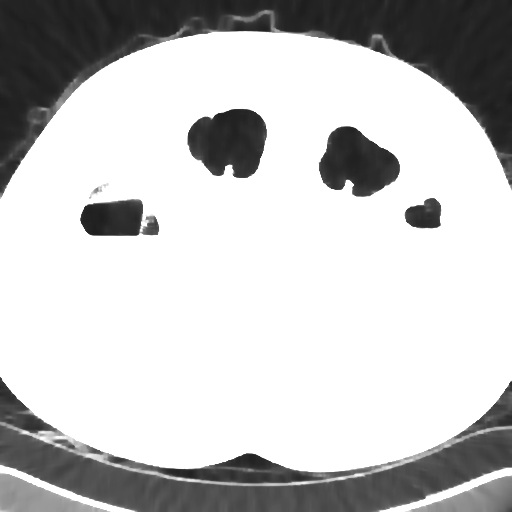

Elimination of noise in ultra low dose CT data

after strong smoothing